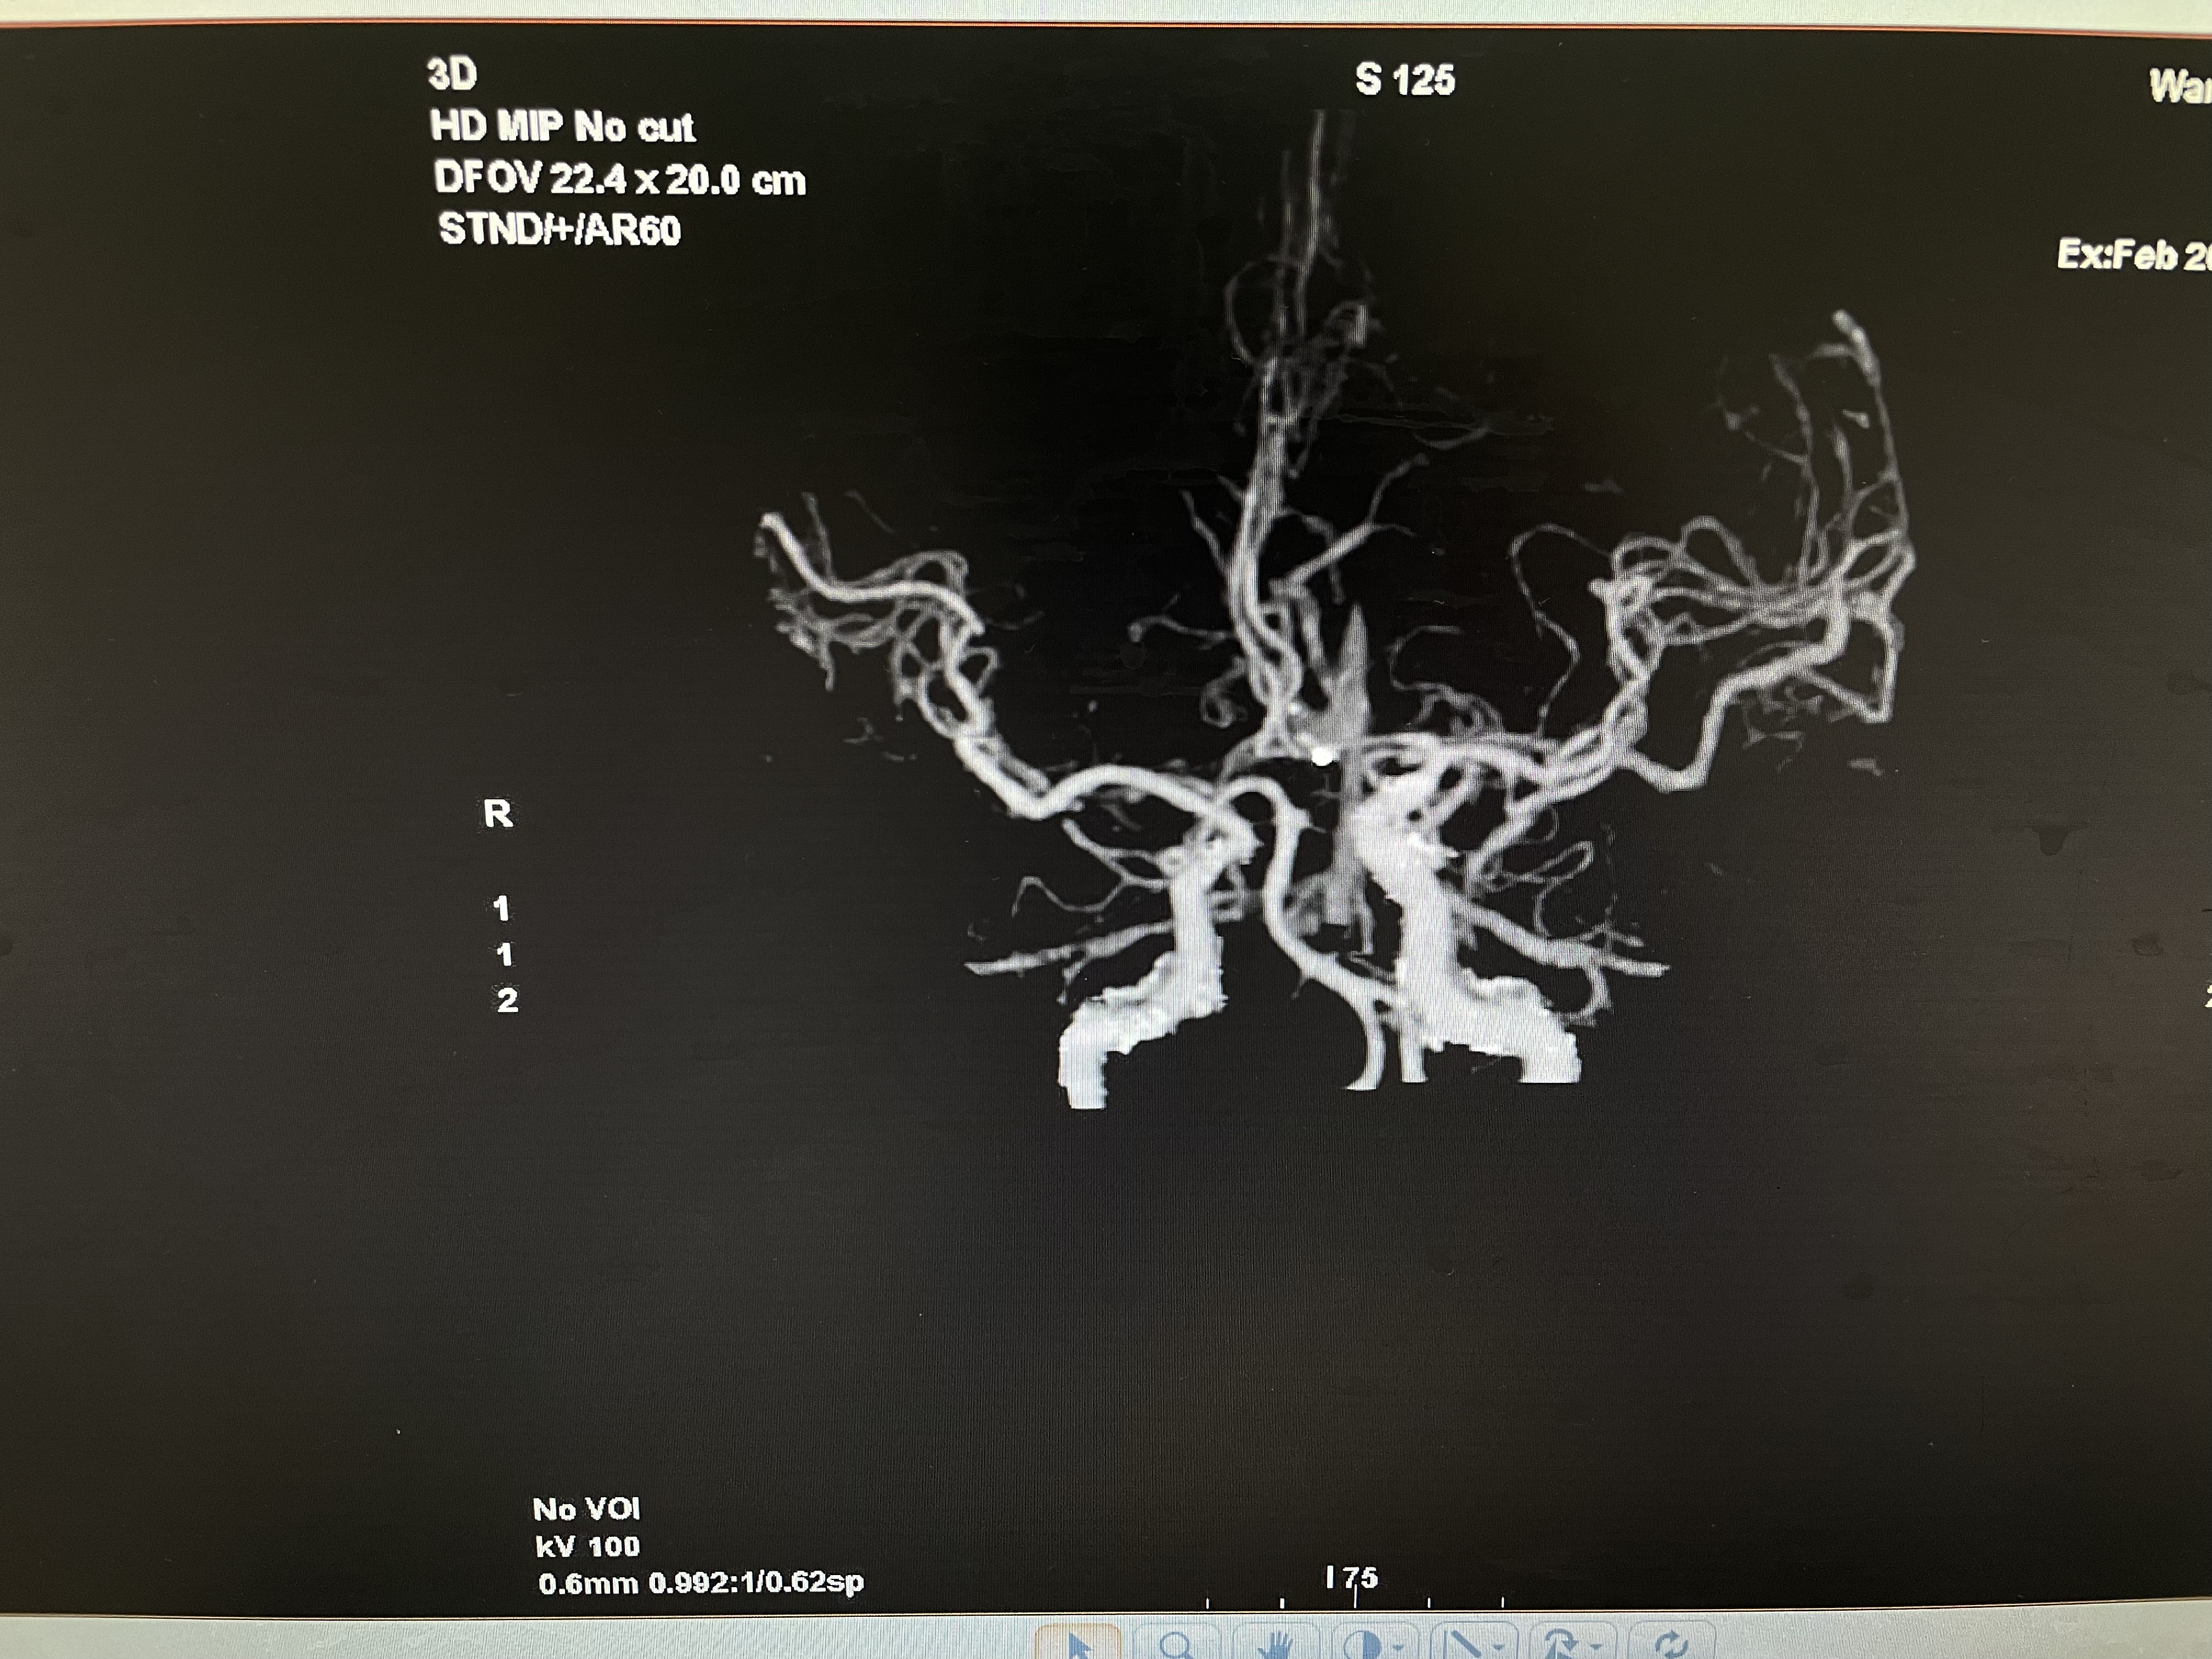

术后CTA

术后CTA